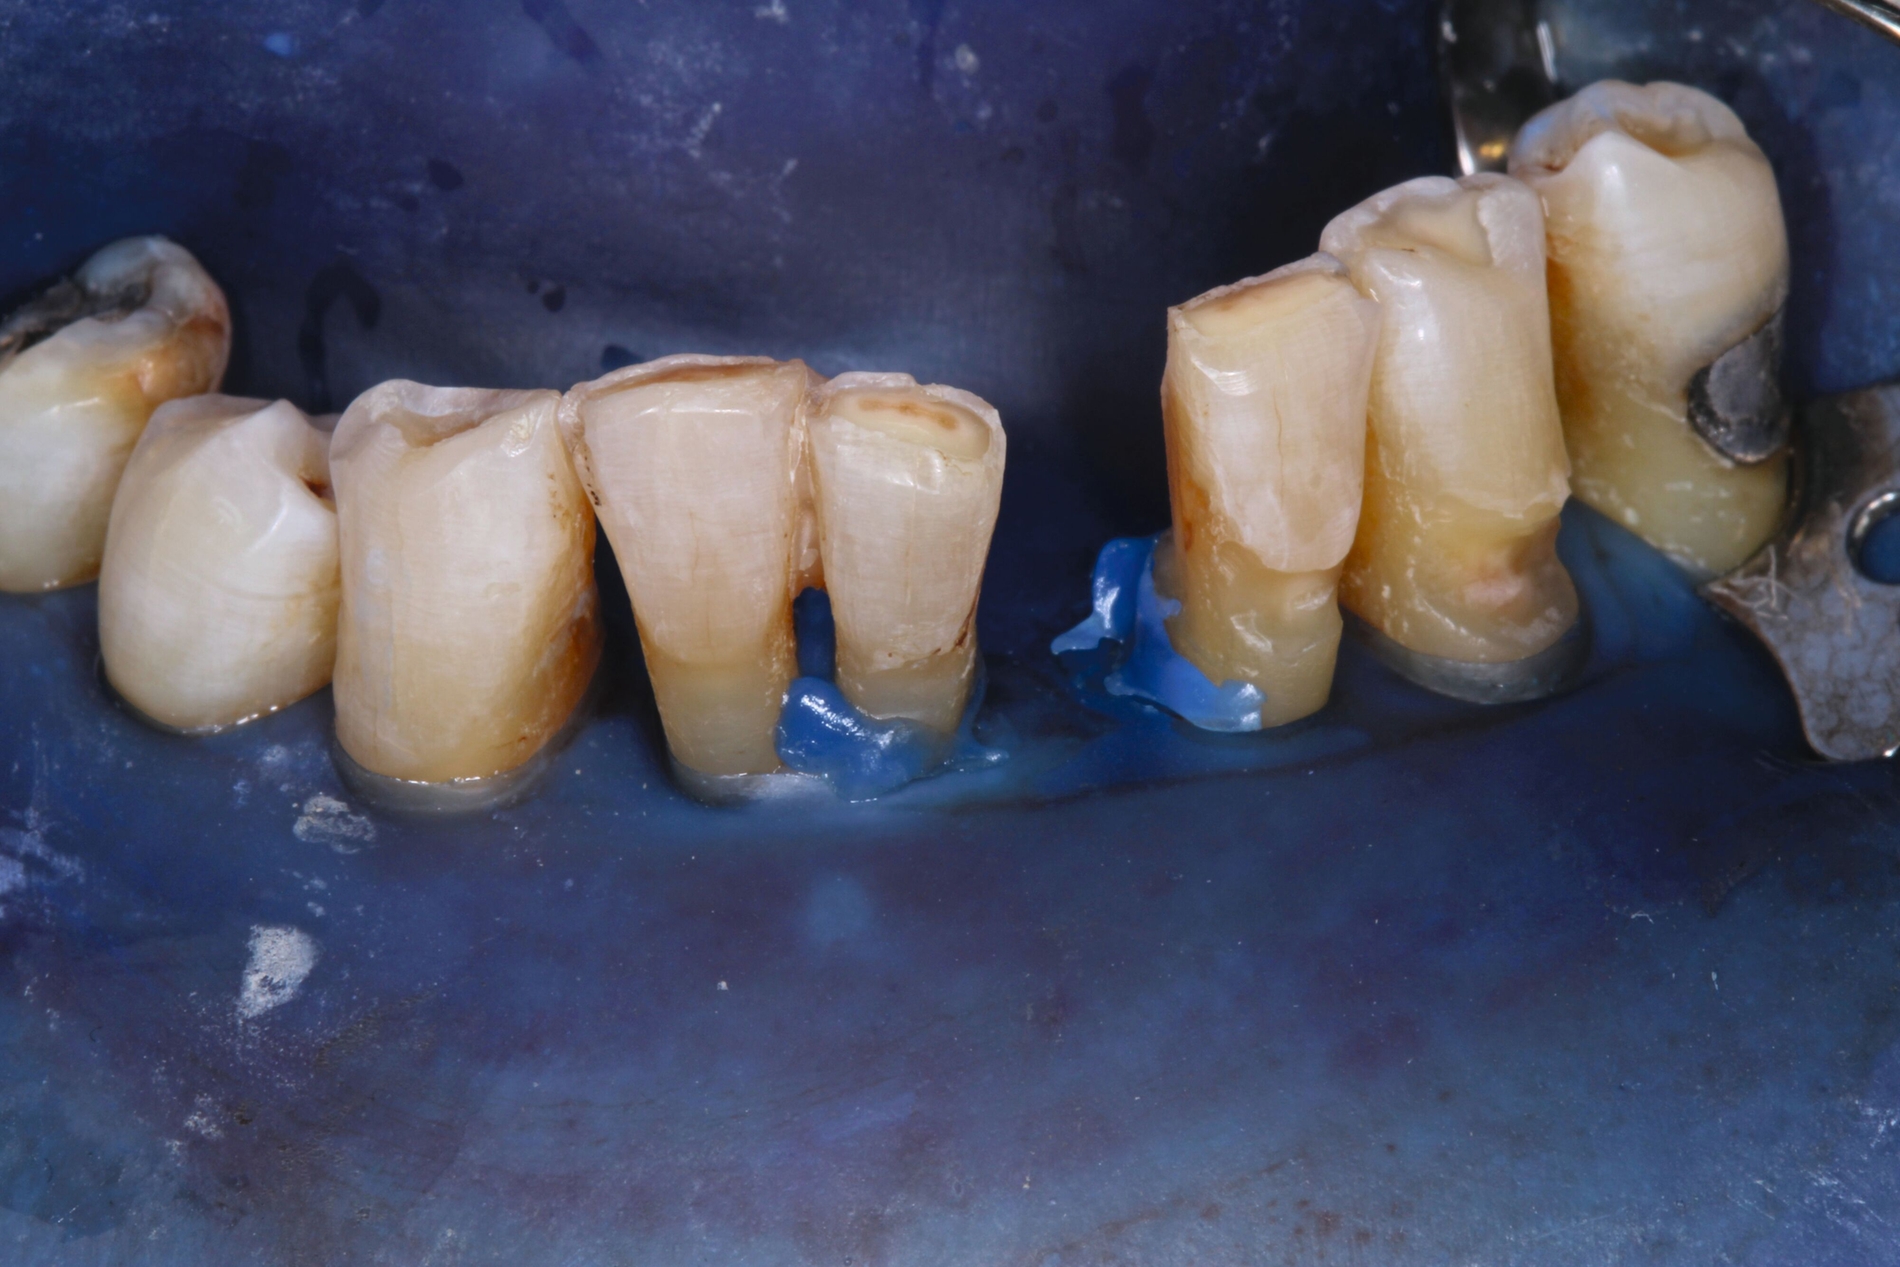

Zahnmedizinische Leitlinien zur zahnmedizinischen Betreuung von geriatrischen und demenziell erkrankten PatientInnen sind aktuell im Entstehungsprozess. Zusätzlich zu den oft komplexen zahnmedizinischen Befunden müssen bei der individuellen Therapieplanung dieser vulnerablen Klientel die Therapiefähigkeit und die Eigenverantwortlichkeit berücksichtigt werden. Dabei ist es weniger das Alter, sondern vielmehr der Zustand der körperlichen und mentalen Funktionsfähigkeit, der den Erfolg zahnmedizinischer Therapien limitiert. Therapien, die bei gesunden Personen jahrelang das Alltagsgeschäft der Zahnmedizin waren, sind bei Personen mit erhöhtem Pflege- und/oder Unterstützungsbedarf eventuell nicht umsetzbar. Gebrechlichkeit (Frailty) ist ein Zustand zwischen guter Gesundheit und Pflegebedürftigkeit im Alter – ein Zwischenstadium, in dem ein vorher fitter älterer Mensch Symptome der Gebrechlichkeit entwickelt und die Gefahr besteht, dass sich sein Zustand verschlechtert. Die geriatrischen Erkrankungen Frailty und auch Demenz sind im Rahmen zahnmedizinischer Behandlungen mit einer reduzierten Kooperations- und Therapiefähigkeit sowie bei der Anfertigung von Zahnersatz mit einer reduzierten Adaptationsfähigkeit assoziiert (Abbildung 3).

Patientinnen und Patienten mit stark reduzierter Therapiefähigkeit profitieren in besonderem Maß von zeiteffektiven Methoden und Materialien, zum Beispiel Bulk-fill-Kompositen, Reparaturfüllungen, Glasionomerzementen oder Intraoralscans. Die Therapiefähigkeit kann – ähnlich wie in der Kinderzahnmedizin – durch ein vertrauensvolles Verhältnis optimiert werden. Anders als in der Kinderzahnmedizin gibt es in der Alterszahnmedizin aber keine altersassoziierten Kontraindikationen für zahnmedizinische Interventionen. Voraussagbare Therapieergebnisse sind von besonderer Bedeutung, um erneute Behandlungen zu vermeiden. Das gesamte Spektrum zahnmedizinischer Interventionen kann bei der Behandlung von Personen mit Pflegebedarf sinnvoll sein. Die Abbildungen 6 bis 9 zeigen zahnmedizinische Interventionen bei Personen mit ausgeprägter Frailty (Stufe 7 der klinischen Frailty-Skala).